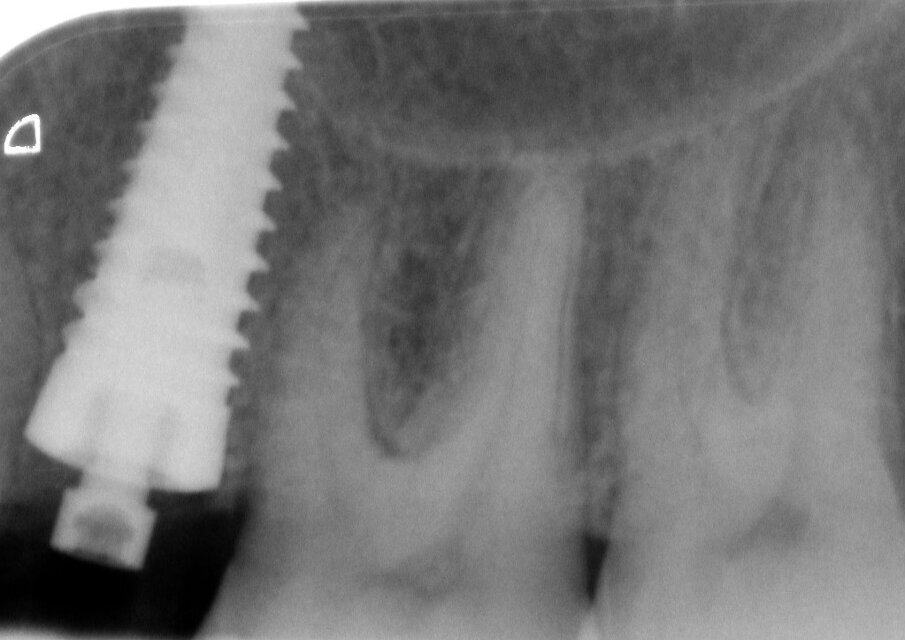

La radiografia mostra il posizionamento dell’impianto (Fig. 12). Sul pilastro di guarigione è stato montato uno ScanPeg (Fig. 13), ed è stata presa un impronta digitale del sito con uno scanner intraorale (Fig. 14). La CBCT effettuata a 3,5 mesi di guarigione (Fig. 15) mostra una buona integrazione dell'impianto Edge e della rigenerazione ossea nel difetto iniziale. L'ISQ è aumentato fino a 72/79, indicando un'ulteriore buona integrazione. Utilizzando un flusso di lavoro completamente digitale, è stato fabbricato un pilastro in zirconia personalizzato su un Neoss TiBase (Fig. 16) ed è stata montata una corona in zirconia sul pilastro (Fig. 17).